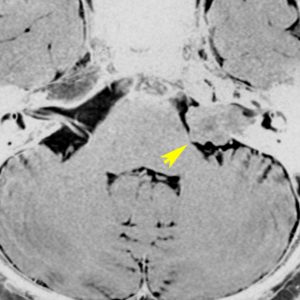

また,この患者さんは急に容態が悪くなって意識障害となりました。何故なら腫瘍の内部で出血したからです(黄色の矢印の部分)。第4脳室が詰まって閉塞性水頭症になって側脳室が拡大しています(右の画像)。